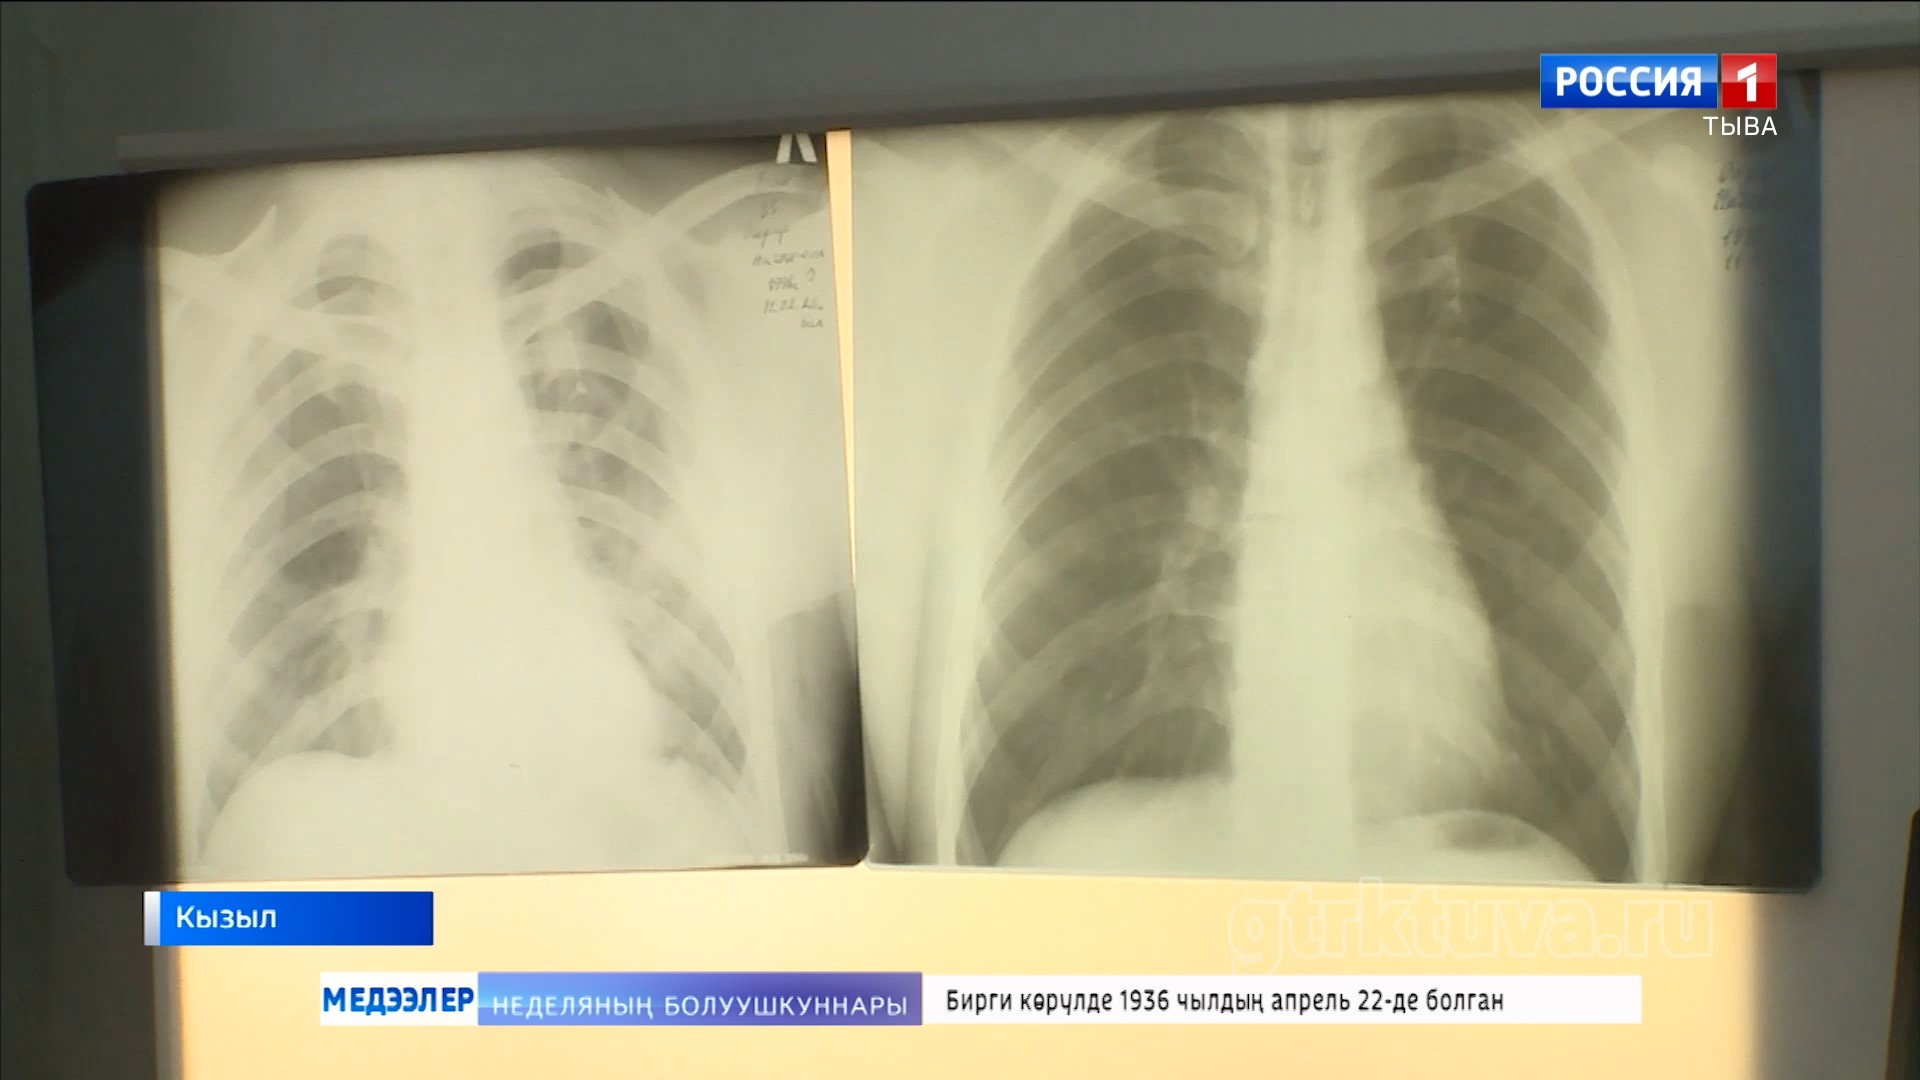

Тыва Россияда өкпе аарыының талазы-биле мурнуку одуругларда хөй чылдарның дургузунда чоруп орарын статистика көргүзүп турар. Социал аарыгларга хамаарыштырып турган туберкулез уе-шагның аайы-биле база өскерлип турар. Чогуур ужурлуг дериг-херексел, эм-таң-биле эмнелге хандыртынып турар. Удавас чаа оран-саваны база тудар. Эң кол чүве, аарыгны эмнээри берге-даа болза, үзе эмнеттинер, чүгле кижиниң бодунуң күзелинден хамааржыр. Аарыгны болдурбазы-биле профилактиканы чорудары чугула.

Март 24-те бүгү делегейде туберкулезка удур демисел хүнү. Аңаа тураскаадып, республикада өкпе аарыынга удур шалыпчы айны чарлаан. Фтизиатрлар көжүп чоруур мобильдиг хөрек тырттырар дерилгелиг автомашина-биле кожуун, сумуларны эргий кезип, найысылалдың аңгы-аңгы микрорайоннарынга чурттакчы чонну шинчилеп, көөр.